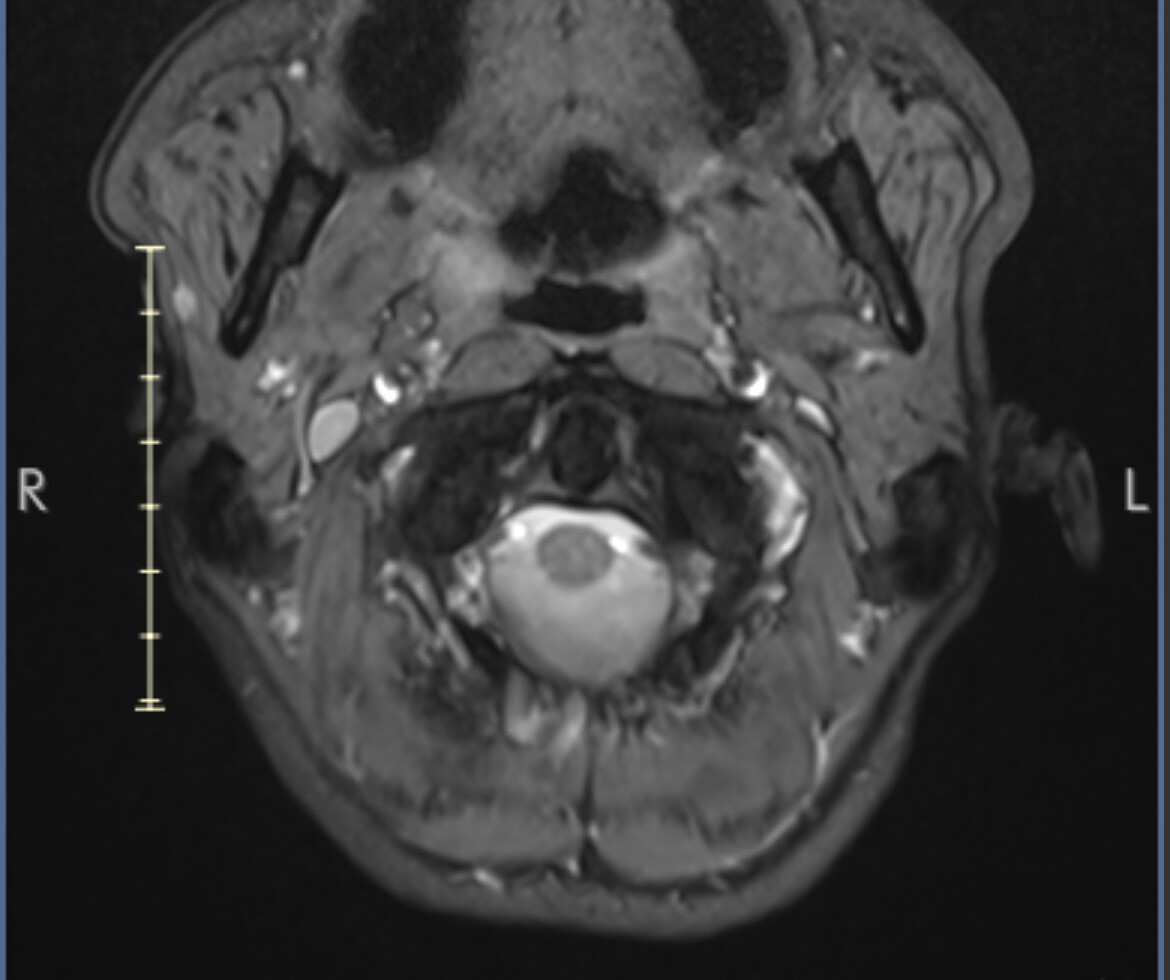

I marked the images for you and marked the IJV.

So you can see how the IJV passes by the transverse processes of C1 which are compressing. In this position the right IJV does not have severe compression, but in Figure 2 you can see that the left IJV is almost invisible, and in the other images there is significant narrowing.

On MRI, it is very difficult to see the styloid processes.